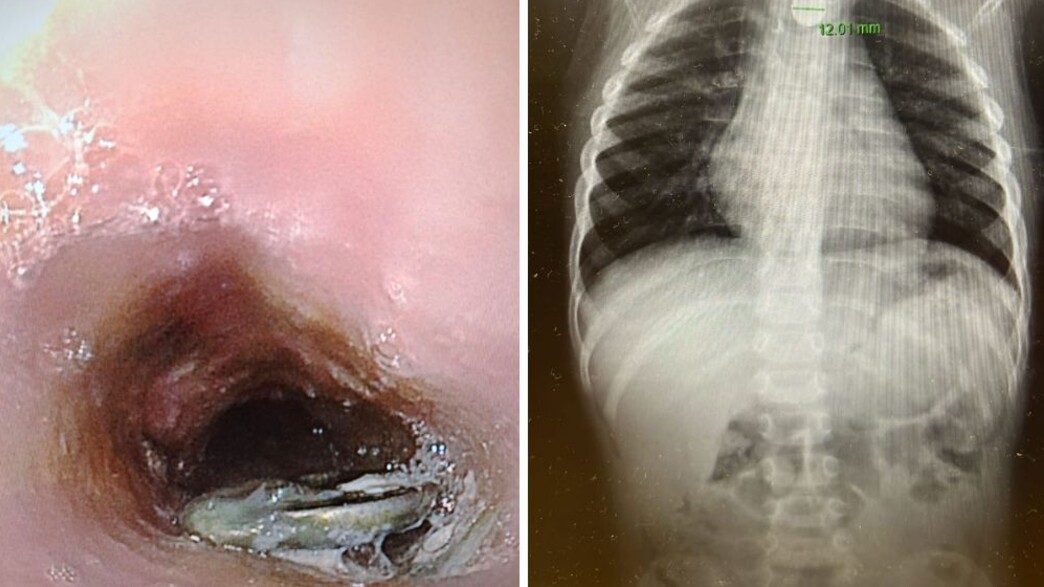

במלר"ד הילדים התקבל הפעוט על ידי ד"ר אהוד רוזנבלום, מנהל המלר"ד, ומיד בוצע לו צילום חזה שבו זוהתה סוללת דיסק התקועה בוושט - ממצא המחייב טיפול דחוף.

בעקבות הממצאים, הוזעק ד"ר אייל זיפמן, מנהל שירות גסטרואנטרולוגיה ילדים במרכז רפואי מאיר, והוחלט להכניס את הילד במהירות לחדר ניתוח. "הסוללה נמצאה נעוצה בוושט ונשלפה בשלמותה באמצעות גסטרוסקופיה, פעולה אנדוסקופית שבה מכניסים מצלמה דרך הפה לדרכי העיכול העליונות. מסביר ד"ר זיפמן. "לאחר הוצאת הסוללה שטפנו את הוושט במטרה להקטין את הפגיעה ההמשכית של החומרים המופרשים מהסוללה. למרות שעבר זמן קצר מרגע הבליעה עד להוצאת הסוללה כבר נוצר כיב בוושט. לשמחתנו בזכות התגובה המהירה של ההורים והפעולה המהירה לא נוצר נזק משמעותי יותר".